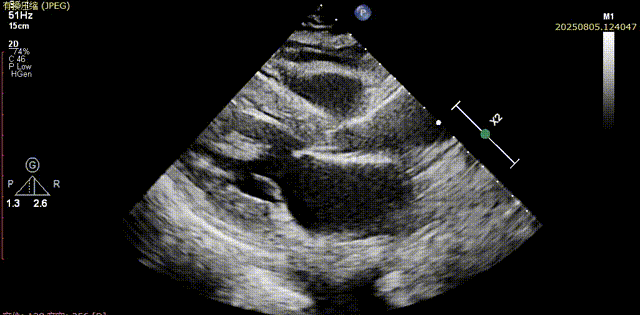

输送器顺利跨瓣,部分释放后,可见喇叭口结构,开始定位释放,180次/分起搏下展开至工作位,超声评估可见位置可,二尖瓣活动良好,瓣周反流较少,综合考虑瓣膜锚定良好,脱钩释放

输送器跨瓣

瓣膜展开至工作位

工作位评估1

工作位评估2